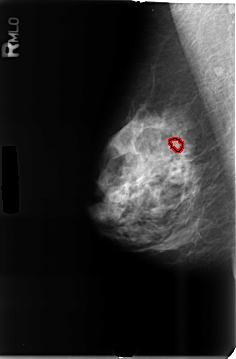

B_3464_1.RIGHT_MLO

FILE: B_3464_1.RIGHT_MLO.OVERLAY

TOTAL_ABNORMALITIES 1

ABNORMALITY 1

LESION_TYPE CALCIFICATION TYPE AMORPHOUS DISTRIBUTION CLUSTERED

ASSESSMENT 3

SUBTLETY 3

PATHOLOGY BENIGN

TOTAL_OUTLINES 1

BOUNDARY

RIGHT_MLO LINES 4656 PIXELS_PER_LINE 3064 BITS_PER_PIXEL 12 RESOLUTION 50 OVERLAY